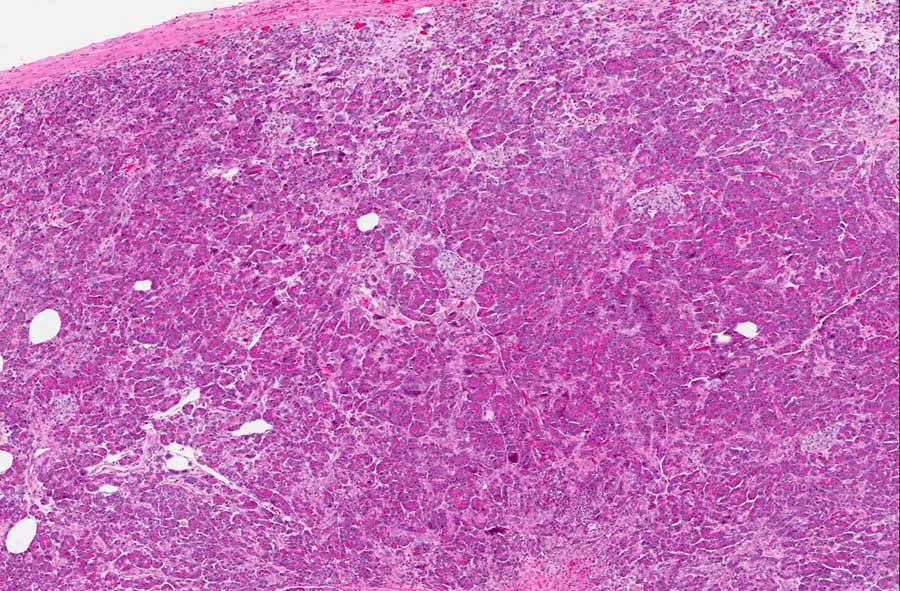

Area 1: The background is very fibrotic and is infiltrated by clusters of neoplastic epithelial cells (adenocarcinoma cells) (arrows). Note that these cells have enlarged nuclei, variation in nuclear size and shpae, and do not have the normal architecture of the normal pancreatic ducts.

Hematoxylin & eosin

• The tumor is composed of clusters of neoplastic glandular cells in a background of fibrosis (Area 1). The invading cells varies from small clusters to single cell invasion. The level of differentiation is well to moderate. Mucin formation is common in among the neoplastic cells. These cells are invasive because they do not respect the boundary and invade into the fibrous stroma.